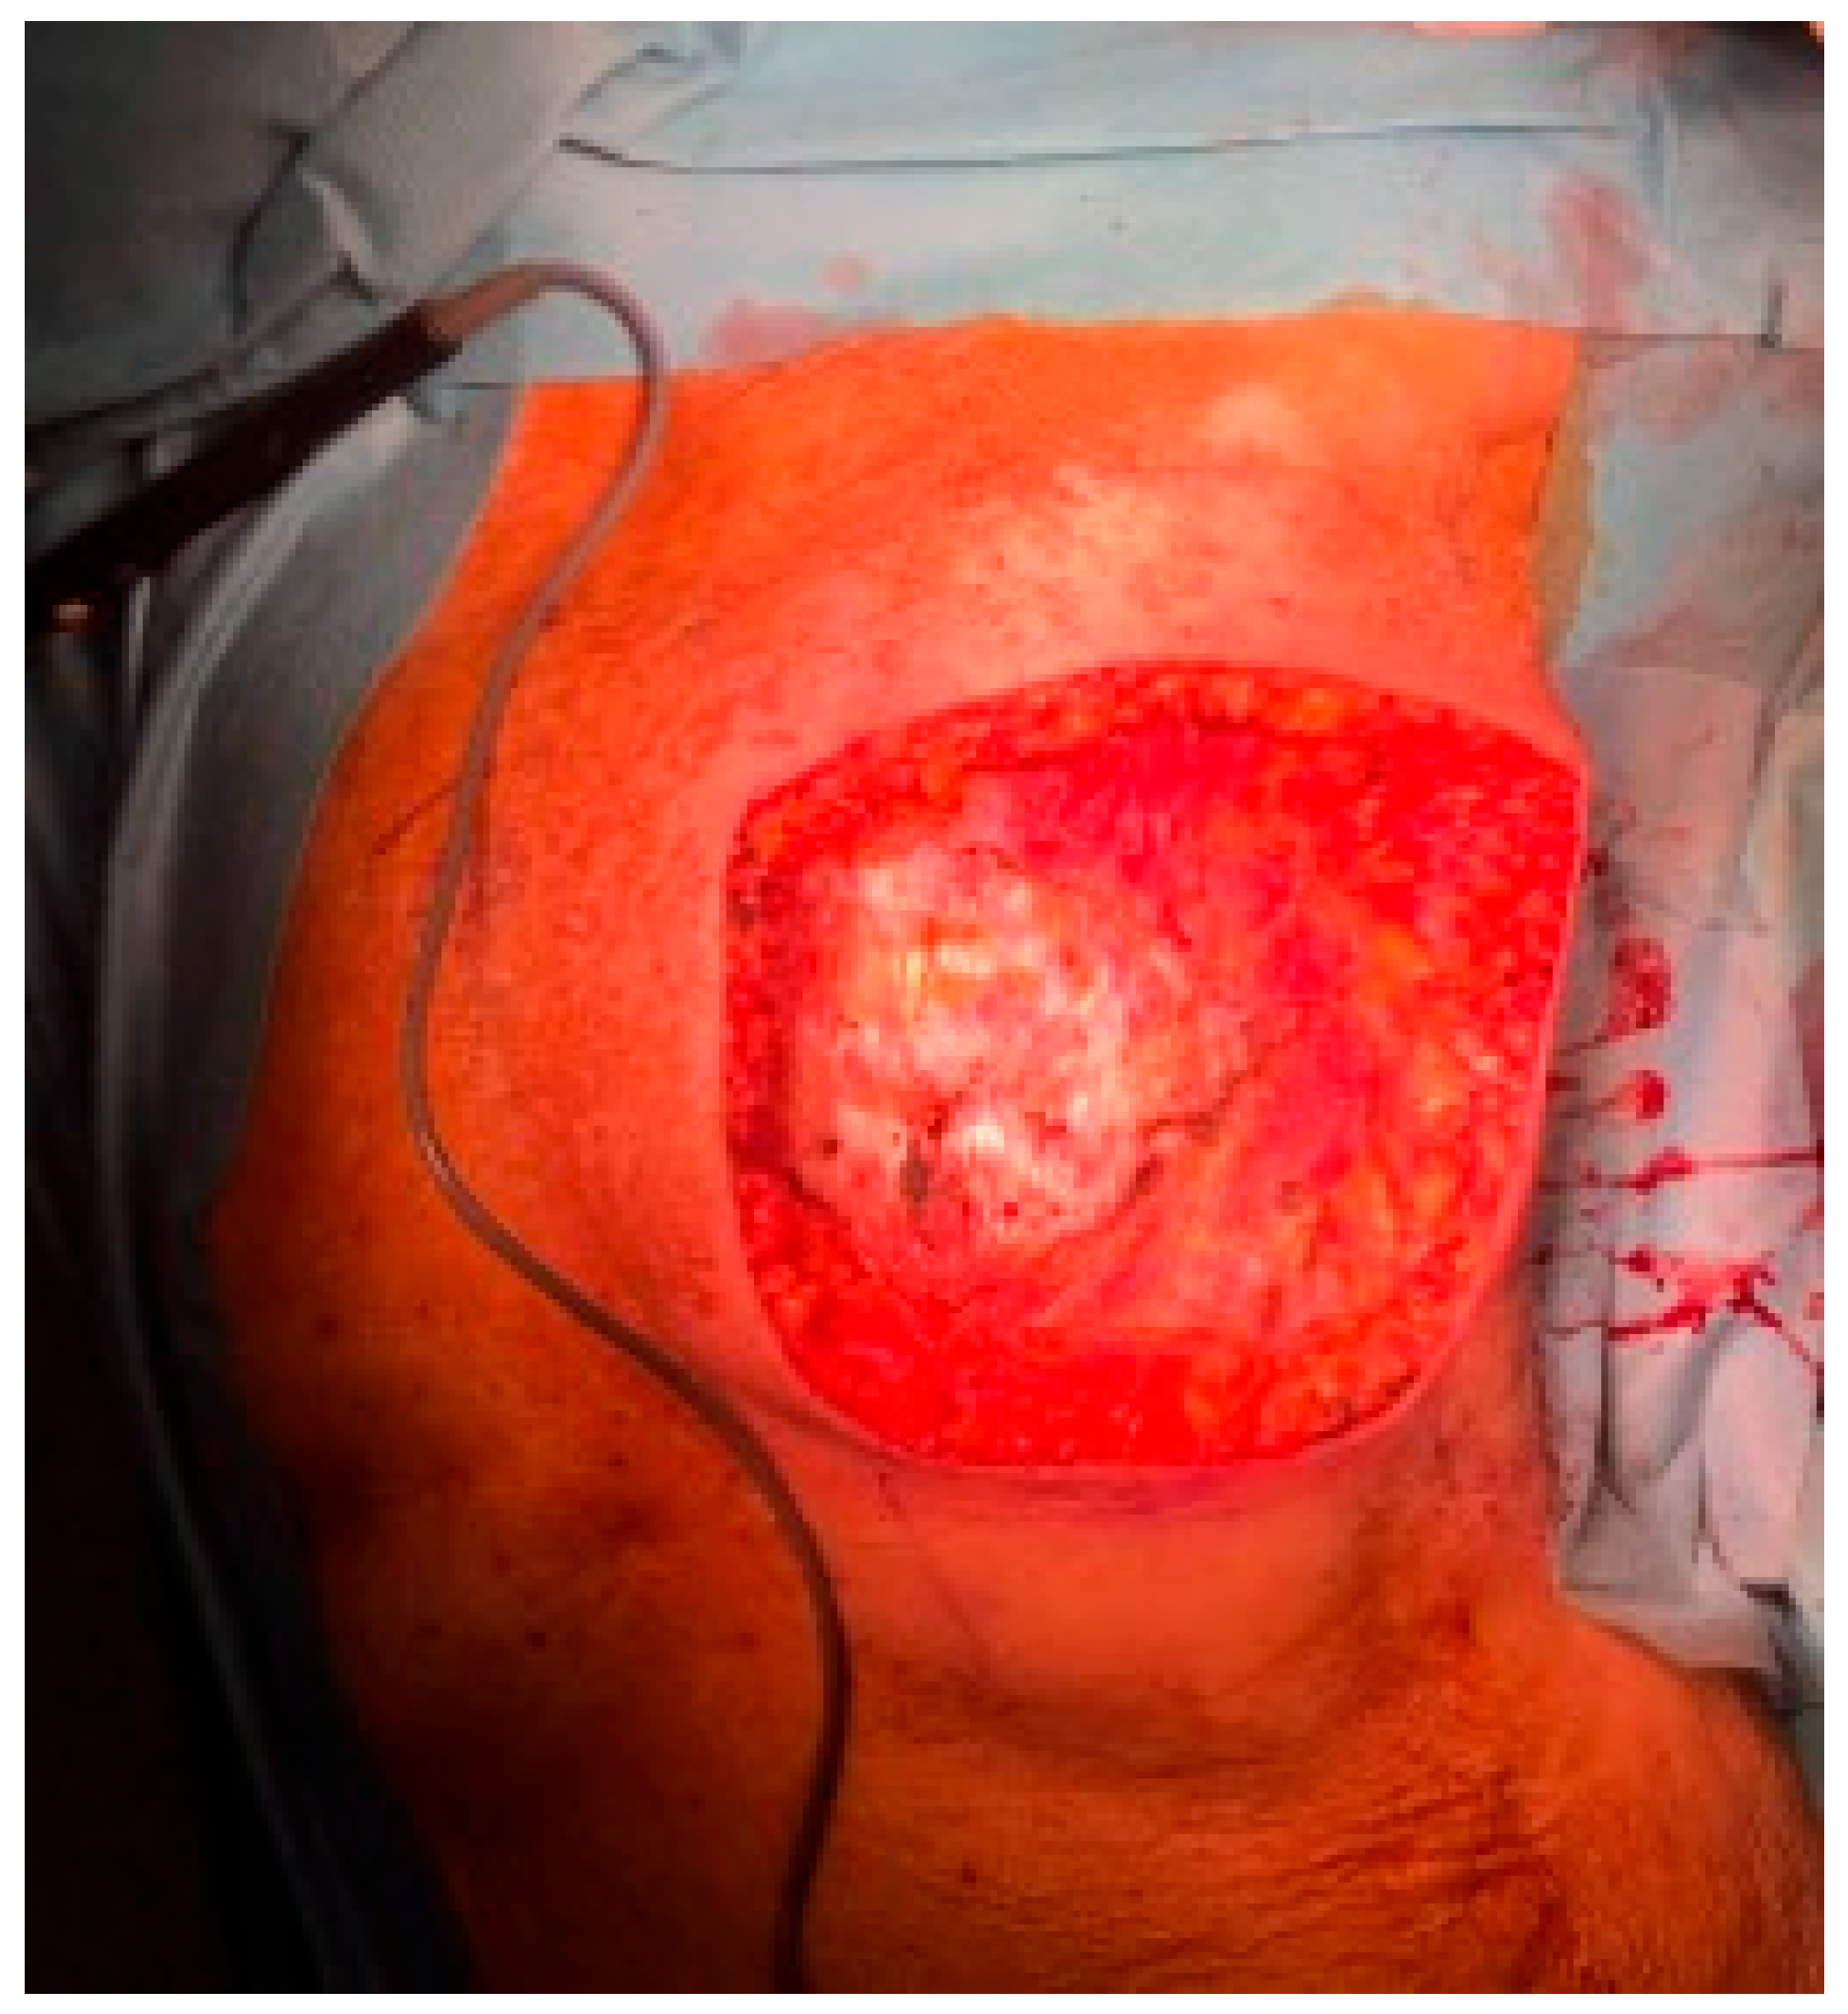

2. Case Report